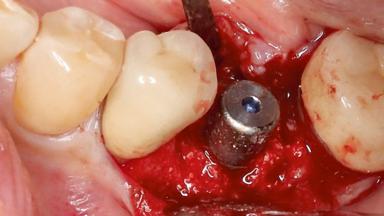

Surgical Management of Peri-Implantitis: Reconstructive Surgical Treatment with Three-Year Follow-up After Treatment

Despite anti-infective surgical treatment, some patients may experience recurrent infection and progressive bone loss requiring additional treatment. Removal of Implant Due to Recurrent Infection describes a conservative approach using an implant retrieval tool without the need for excessive bone removal or use of a trephine.

A 70-year-old female patient was referred by her general dentist to the periodontist for assessment and management of an infection associated with implant 36. The general dentist had noted suppuration on probing during examination.